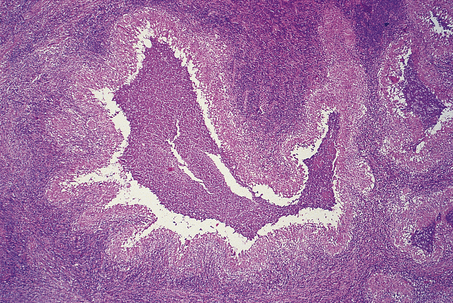

Nodular sclerosis

The term nodular sclerosis describes many of the histological features of this, the commonest subtype of classical Hodgkin’s lymphoma (75% of cases). The normal lymph node architecture is replaced by cellular nodules which are separated by bands of collagen (Fig. 22.8). Within the cellular nodules is a mixed infiltrate similar to other types of Hodgkin’s lymphoma but containing a distinctive Hodgkin’s cell variant termed the lacunar cell. The lacunar cell is so named because it appears to sit in a space or ‘lacuna’, caused by the disappearance of its lipid-rich cytoplasm during the process of creating a paraffin block of the tissue. It possesses the large nucleus and prominent eosinophilic nucleolus seen in other Hodgkin’s cells.

image

Fig. 22.8 Nodular sclerosing Hodgkin’s lymphoma. image The cellular nodules are surrounded by thick collagen bands. image Lacunar cells (Hodgkin’s cell surrounded by a clear space) are characteristic of nodular sclerosing Hodgkin’s lymphoma.

Nodular sclerosis is a distinctive form and does not transform into any of the other subtypes of classical Hodgkin’s lymphoma. However, the cytological composition of the cellular nodules may vary from one in which the predominant cell is the small lymphocyte, with only scanty lacunar and Reed–Sternberg cells, to a histological picture that is dominated by Hodgkin’s cells with depletion of lymphocytes. This latter form has been correlated with an aggressive natural history and is termed grade 2 nodular sclerosis; all other histological subtypes are classified as grade 1 nodular sclerosis.